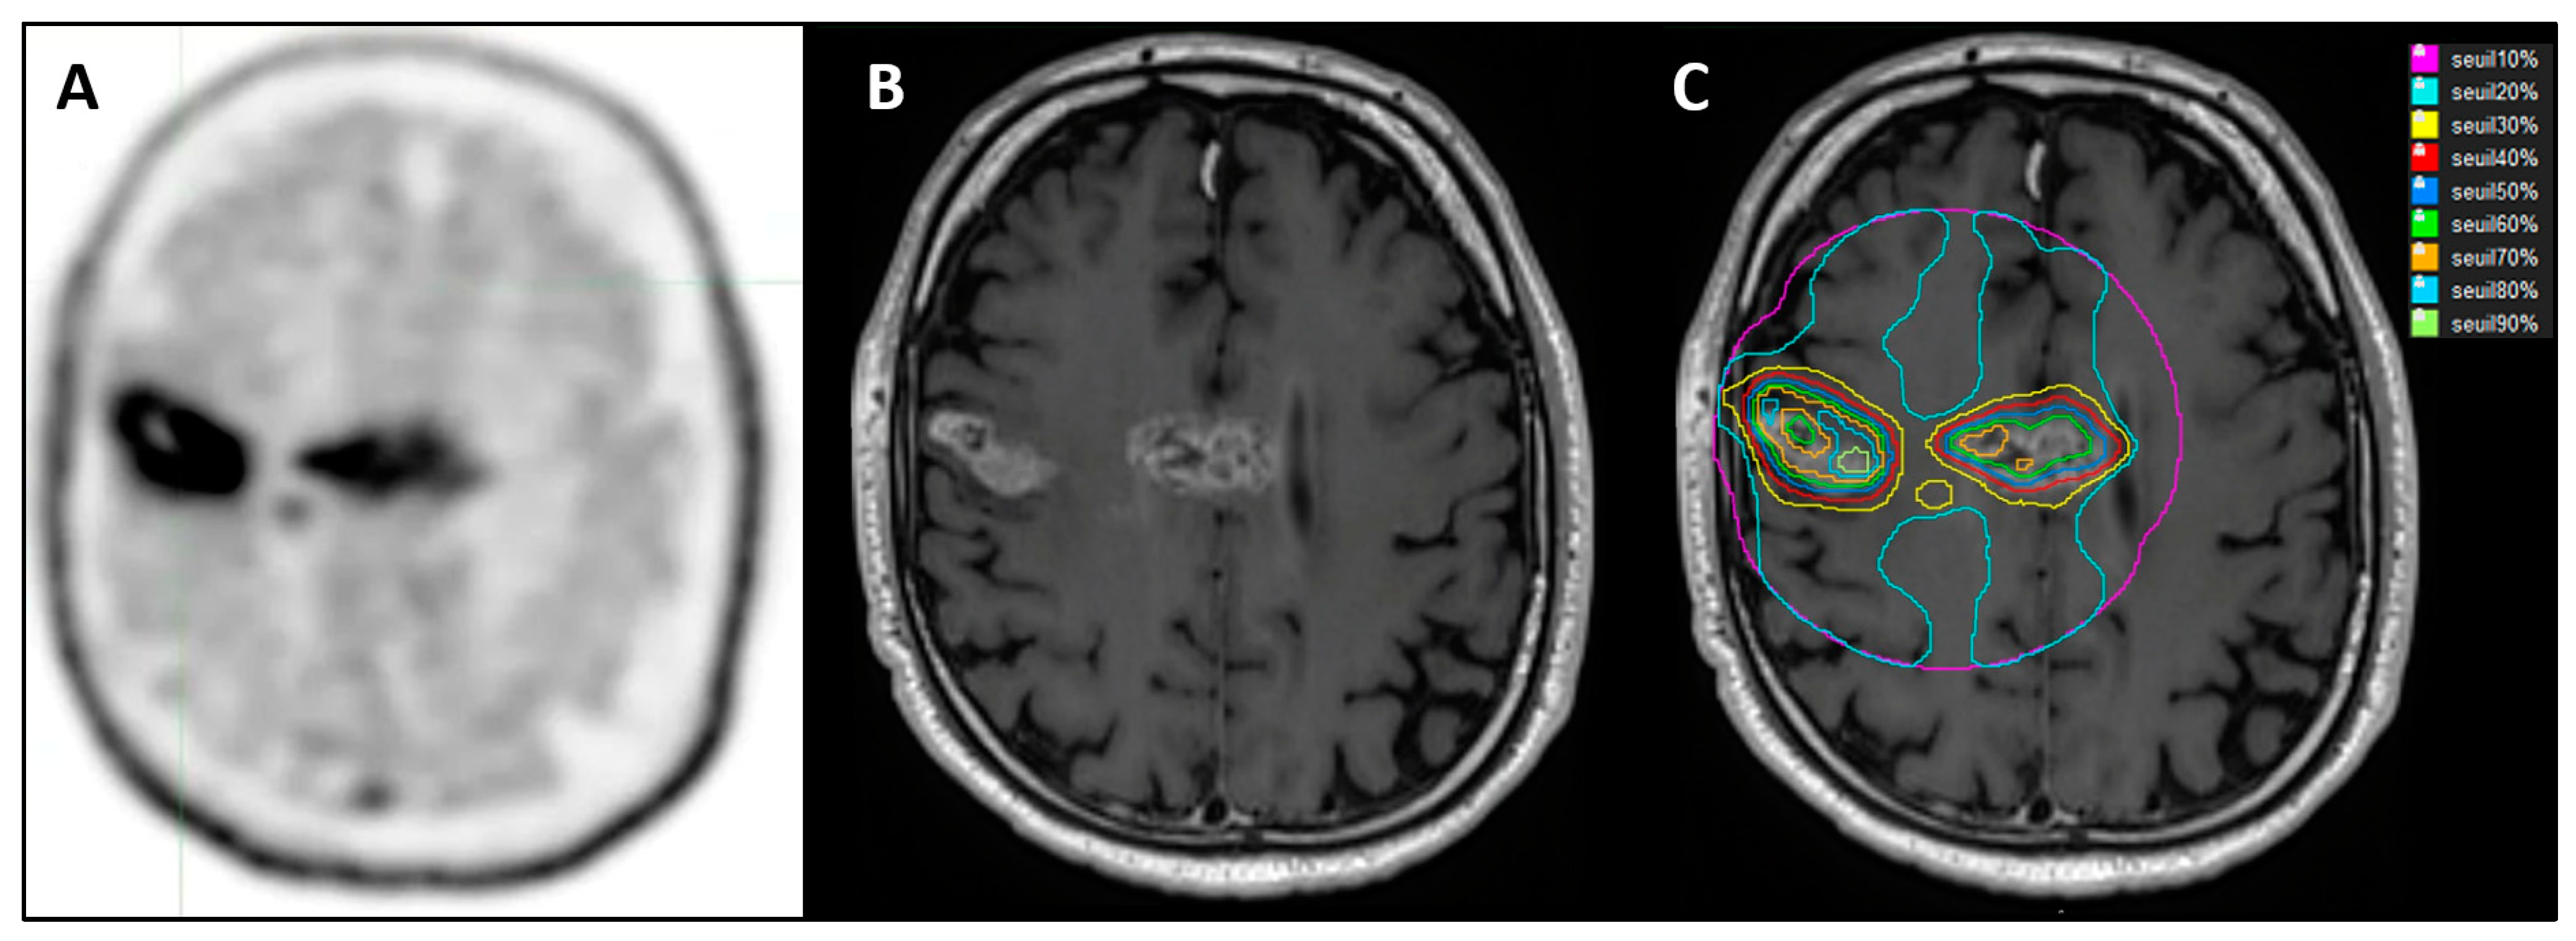

% SUVmax method = Application of several relative SUVmax thresholds, defined as a three-dimensional contour around voxels equal to or greater than x% (x = 30, 40, 50, 60, 70, 80, and 90) of tumor SUVmax. The 10 and 20% SUVmax thresholds were not included in the data analysis due to outlier results (Figure 3).

Figure 3. A 68-year-old patient with multifocal glioblastoma in the right frontal area and corpus callosum. (A). FET PET after surgical biopsy and before RT-CT. (B): NADIR MRI (MRI 2) after RT-CT in T1-GD sequence 3 months after FET PET. (C): Different SUVmax thresholds on MRI 2 after co-registration.